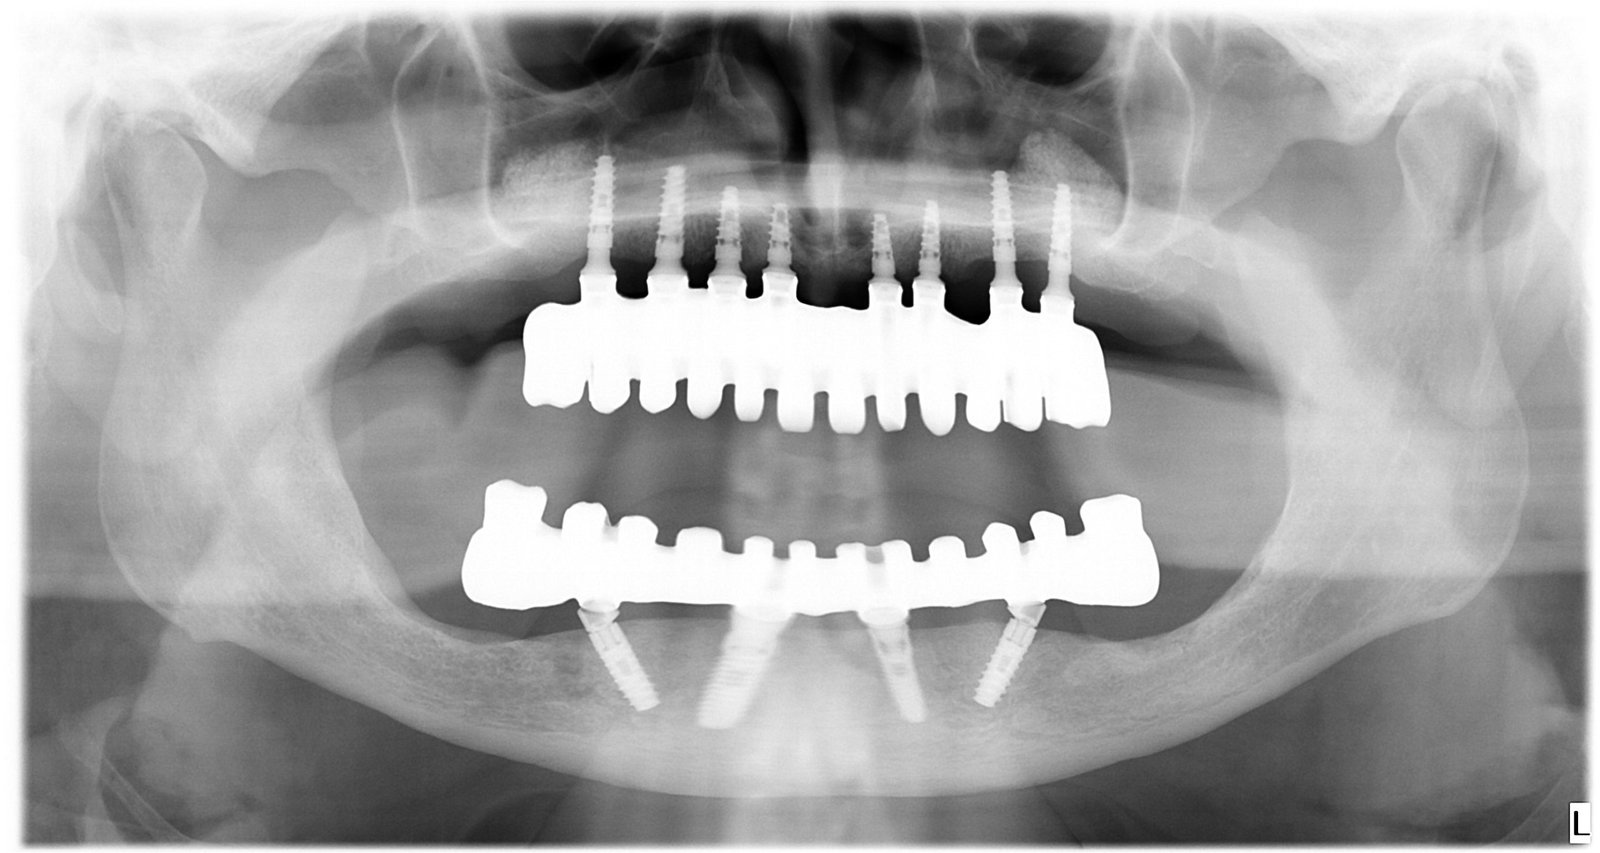

Caso 2 - caso de Carga inmediata

Buscaba una solución rápida y eficaz para volver a masticar y sonreír con normalidad. Mediante carga inmediata conseguimos rehabilitar su boca en una sola intervención, combinando rapidez, estética y funcionalidad.

Se confirma la correcta posición y fijación de los implantes, lo que permite colocar una prótesis fija inmediata con total fiabilidad.